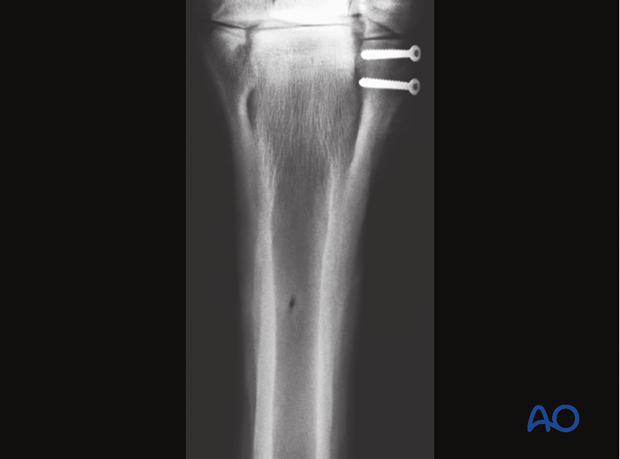

Proximal Fracture of MC IV - 6-hole 3.5 one-third Tubular Plate

A 3.5 mm (narrow) DCP, LC-DCP or LCP, third-tubular plate or reconstruction plate (LCP/DCP) is appropriate in most cases.

Usually a 5-hole plate can be used. The distal part of the splint bone becomes very thin, which prevents the use of a longer plate in most horses.

The plate is positioned on the palmaro/plantaro-latero/medial side of the splint bone. Special care must be taken to the orientation and location of the plate, so that at least two screws can be inserted on each side of the fractured zone. In the distal part, the screws need to be very short to avoid protrusion into the third metacarpal/-tarsal bone.